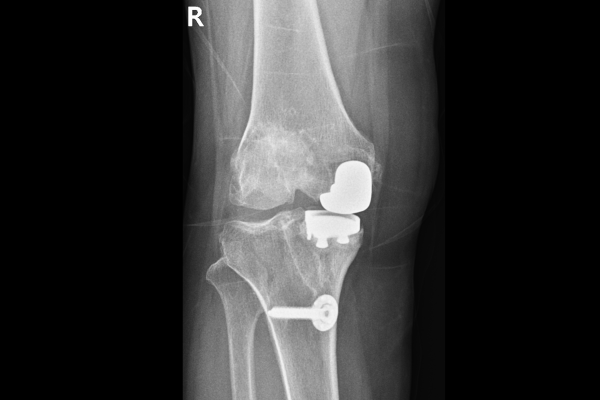

수술 후 다리 정렬을 보면 일자로 곧게 체중축이 교정된 것이 확인됩니다.(좌측 무릎도 안좋으셨기 때문에, 우측 재수술 후 약 일주일 뒤에 좌측 무릎 인공관절 전치환술도 시행하였습니다.)

수술 전/후 사진을 비교해보면 다리 정렬이 일자로 곧게, 아주 좋아진 것이 확인됩니다.

인공관절 재치환술은 기존 인공관절을 빼낼 때, 최대한 남은 뼈는 건들이지 않고 인공관절 기구만 깔끔하게 제거하는 것이 중요한 고난이도의 수술입니다. 또한 수술 중간중간 돌발상황이 발생할 수 있기 때문에, 증상이 있다면 무릎에 대한 해부학적 이해도가 높고, 인공관절 수술 경험이 많은 정형외과 전문의를 찾아 정확한 진단과 치료를 통해 건강한 무릎을 되찾기를 바랍니다.(수술 다음날 바로 걷기 시작하는 미라클한 결과를 얻을 수 있습니다.)